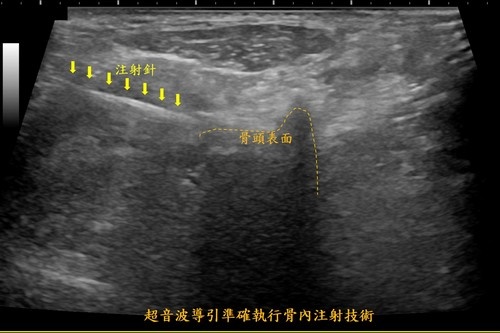

詹女士因為年紀較大,身體修復能力差,另外膝關節需要承受身體重量,相對組織修復就更不容易,骨頭內微小骨折不僅影響到她的日常生活行動力,心情也受到相當大的影響。王柏凱主任說,經過與病人和家屬的討論後,決定改以新引進的療法「骨內注射」來改善疼痛,直接注射在患部上來修復受損部位。

圖說:花蓮慈濟醫院麻醉部疼痛科王柏凱主任為詹女士做骨內注射治療